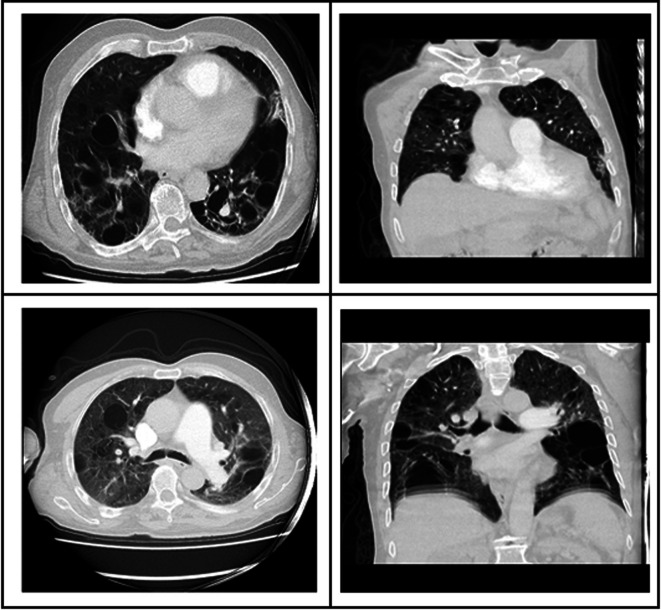

The Importance of Multisystem Evaluation in Diagnosing Birt-Hogg- Dubé Syndrome: A Case Report.

Abstract Image